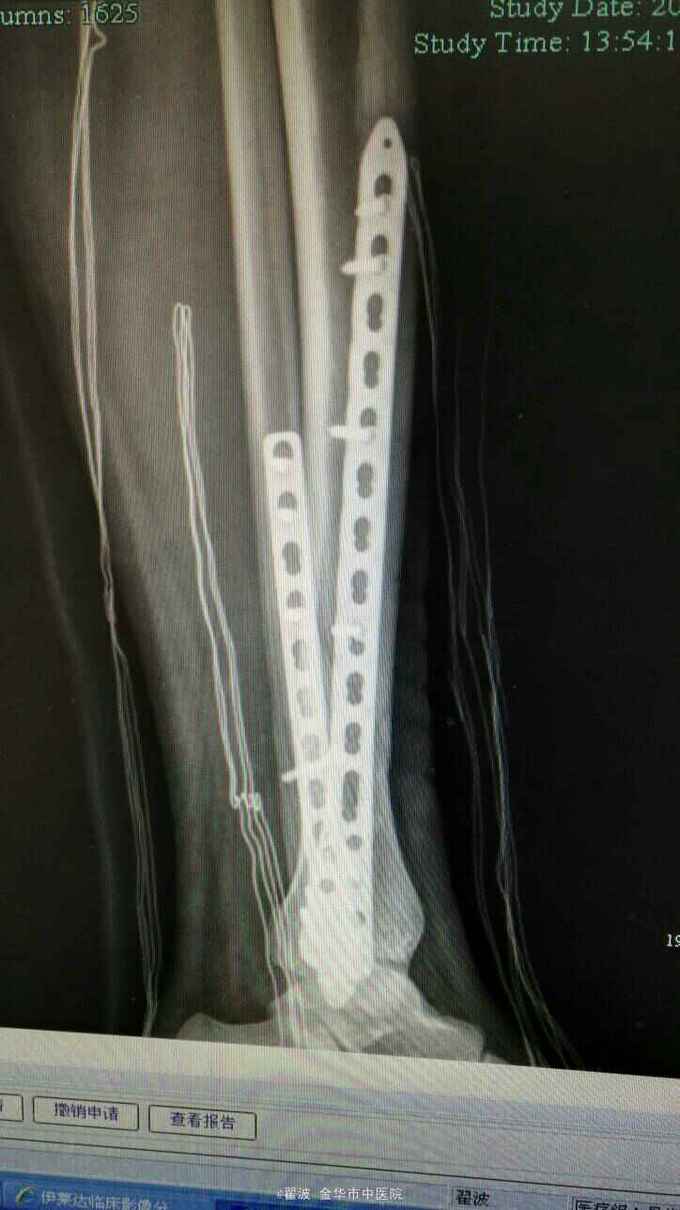

伤后肿胀很明显,可见张力性水泡,出现皱褶才手术。